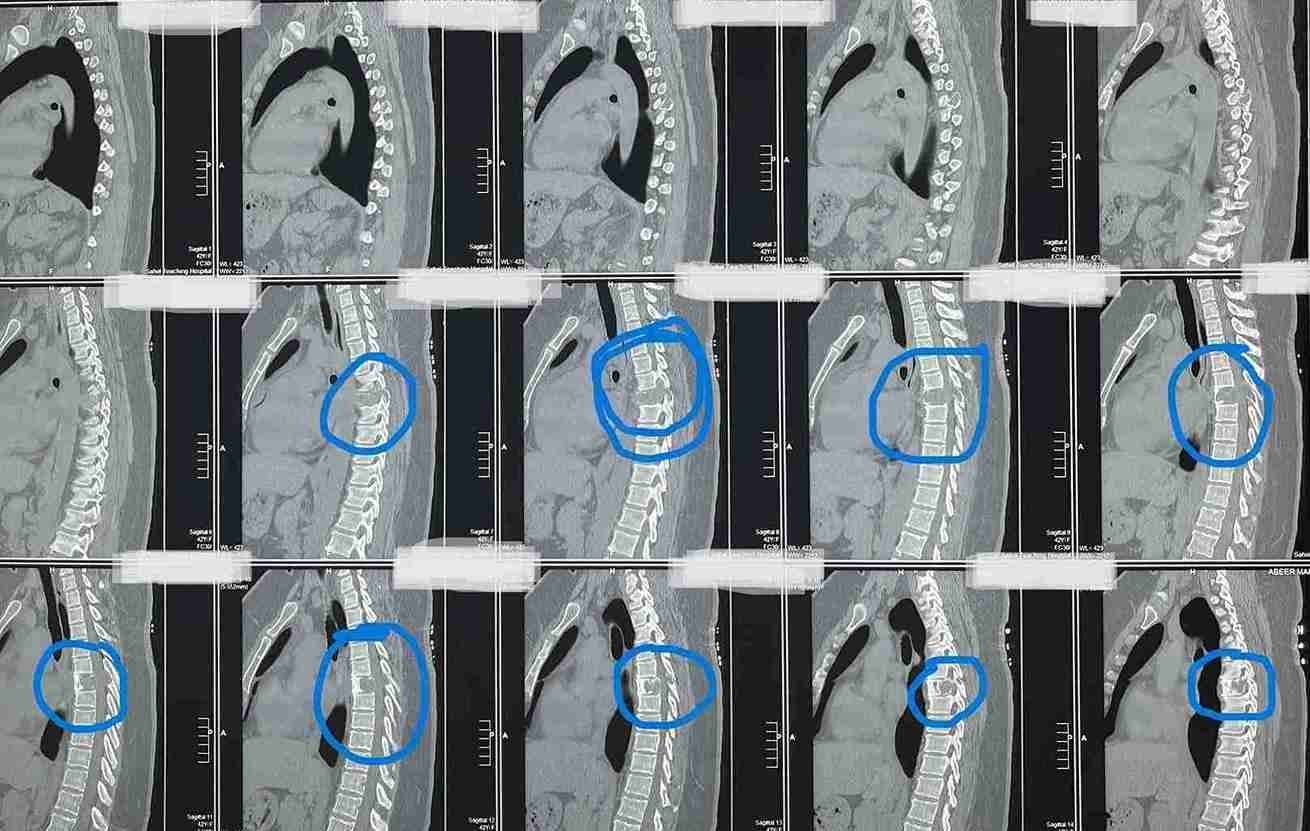

43-year-old female patient suffers from increasing weakness in the lower extremities

A 43-year-old woman suffering from progressive weakness in both lower limbs was diagnosed and treated. This condition affects walking ability and mobility, requiring thorough neurological evaluation to determine the underlying cause and develop an appropriate treatment plan.

• Accurate diagnosis using latest neuroimaging techniques